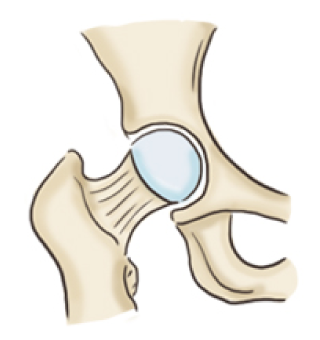

대퇴 골두는 관골과 맞닿아 있는 둥근 부분으로 고관절의 머리 부분을 말합니다.

대퇴골두에 혈류가 차단되면 뼈조직이 죽는 괴사가 일어나는데 이를 '대퇴 골두 무혈성 괴사'라고 진단합니다.